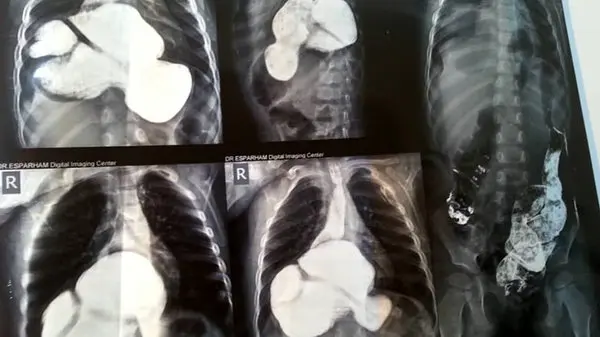

او ادامه داد: با توجه به تداوم وضعیت بیمار، دستگاه گوارش او مورد بررسی قرار گرفت که پس از این آزمایش مشخص شد در رویدادی نادر معده و قسمتی از رودهها به علت نقص در دیواره دیافراگم در قفسه سینه بیمار است.

معاون درمان دانشگاه علوم پزشکی تربت حیدریه گفت:این عارضه از بدو تولد همراه بیمار بوده است پس از انجام مراقبتهای اولیه، جراحی بیمار در بیمارستانی در مشهد مقدس انجام شد و هم اکنون نیز حال عمومی این کودک ۲ ساله مطلوب گزارش شده است.